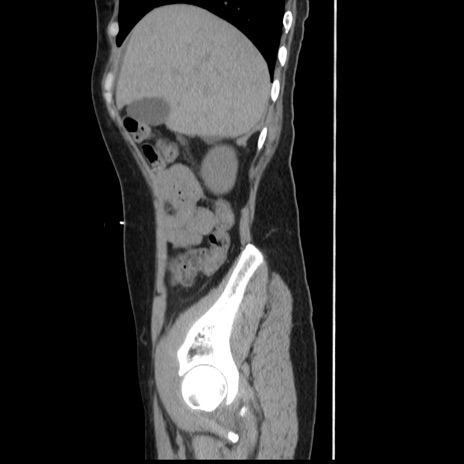

症例

【症例】 50歳代女性

【主訴】 腹痛

【現病歴】前日生レバーを食べた。今朝に排便あり。 昼前に突然発症の腹痛を生じ、当院救急外来を受診した。

【既往歴】 子宮筋腫にてで子宮全摘後

【身体所見】 意識清明、腹部:平坦、軟、下腹部やや左を中心に圧痛・反跳痛あり、筋性防御あり

【データ】WBC 7800、CRP 0.07

冠状断像